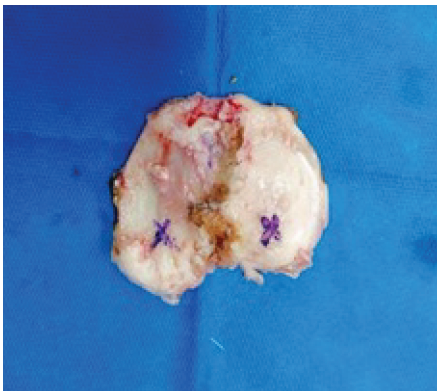

Manual in vitro verification of the bone cuts (Fig. 3) was performed after the resections, following the methodology outlined by Seidenstein et al., [5]. A digital vernier caliper was used to measure the depth of the cuts, which was then compared with the pre-operative plan for accuracy. The jaws of the vernier caliper were kept exactly at the resection landmarks placed during the pre-operative planning (posterior one-third of the medial and lateral aspects of the tibial plateau and the proudest point of the distal femur) (Fig. 4 and 5).

Figure 3: Manual verification of bone cuts (tibia and femur) using a digital vernier caliper. TM: Tibia medial, TL: Tibia lateral, DM: Distal femur medial, DL: Distal femur lateral.

Figure 4: The jaws of the vernier caliper are being positioned at the approximate locations of the resection landmarks identified during segmentation and planning.

Figure 5: Approximate position where the resection landmarks were marked during segmentation and planning.